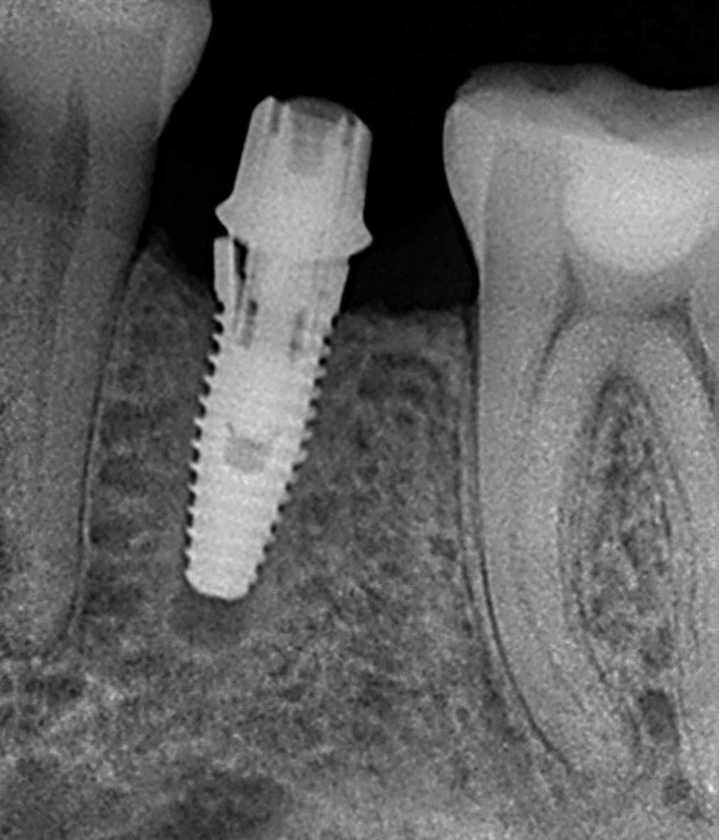

Implants with internal hex connections are more prone to failure at the connection than those with external hex connections.28 This is related to the thickness of the metal at the thinnest point between the internal surface of the interface and the external surface at the crestal area of the implant. When overloaded, implants with an internal hex connection may present with fractures at the points of the hex.29 These points are where the metal is the thinnest at the crestal portion of the implant and where stress is concentrated during overloading. This is less problematic in wider diameter implants because the metal is thicker in this area of the implant; however, in standard or narrow diameter implants, fracture may result, causing catastrophic failure of the implant (Figure 1). This may also occur in other internal implant connection types, such as trilobe connections, especially when the crestal thickness of the implant is minimal, leading to fracture of the coronal aspect of the implant (Figure 2). Implants with conical connections are not immune to potential fracture in this area, and the thin walls of some standard or narrow diameter models may split even without the isolated stress points observed in internal hex-, trilobe-, and octagon-type connections (Figure 3).30 Sometimes, fractures of implants at the coronal aspect are not clinically visible but, instead, are identified radiographically either after a patient complaint of pain in the area, due to the presence of soft-tissue inflammation, or during a routine examination with no patient complaint (Figure 4).

(2.) Fracture of the coronal portion of the trilobe connection of a standard diameter implant fabricated from CP-Ti grade 4 related to mechanical overloading.

Figure 2